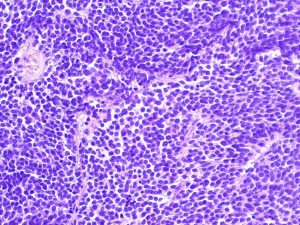

Mehr erfahren zu: "Früherkennung in der Krebs-Nachsorge: Melina Heinemann gewinnt Promotionspreis der Maria-Möller-Stiftung" Früherkennung in der Krebs-Nachsorge: Melina Heinemann gewinnt Promotionspreis der Maria-Möller-Stiftung Ewing-Sarkome bilden durch ihr schnelles Wachstum früh Metastasen aus, 30 bis 40 Prozent der Patienten erleiden ein Rezidiv – und ist es so weit gekommen, ist die Überlebensrate gering. Umso […]